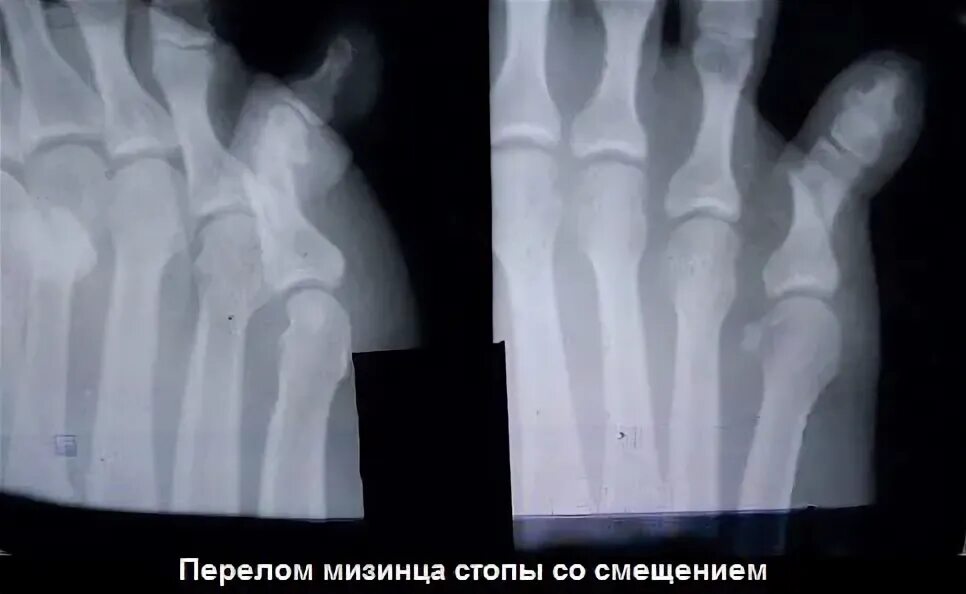

Закрытый перелом пальцев стопы мкб 10